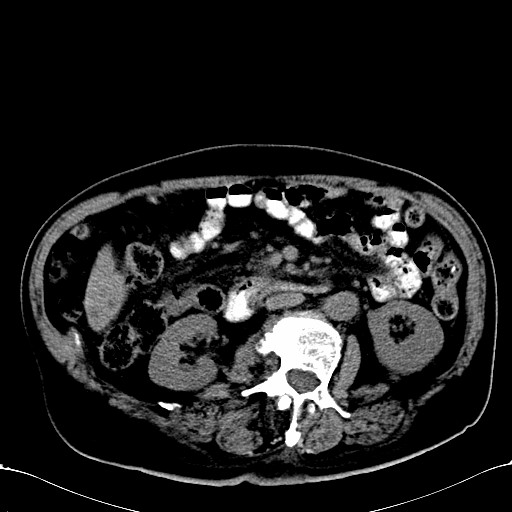

标题: CT28270:胰管扩张,肝多发占位 [打印本页]

标题: CT28270:胰管扩张,肝多发占位

患者,男,75岁。

1)考虑胰头癌并肝脏多发性转移;建议行ct增强扫描检查。2)胃窦癌?建议行胃镜检查。

胃窦癌肝转移

考虑胃窦癌伴肝转移。

胰管显著扩张,但胆总管未见扩张征象,不太符合胰头占位!考虑慢性胰腺炎.胃窦占位并肝内转移可能!mrcp胃镜增强一起上!